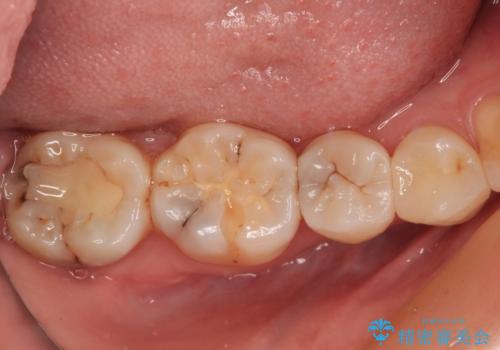

処置を行った歯以外にもむし歯と思われる歯が多数ありますが、費用のかかる治療であれば、優先順位をつけて、処置を急ぐ歯から処置を進めて行きました。